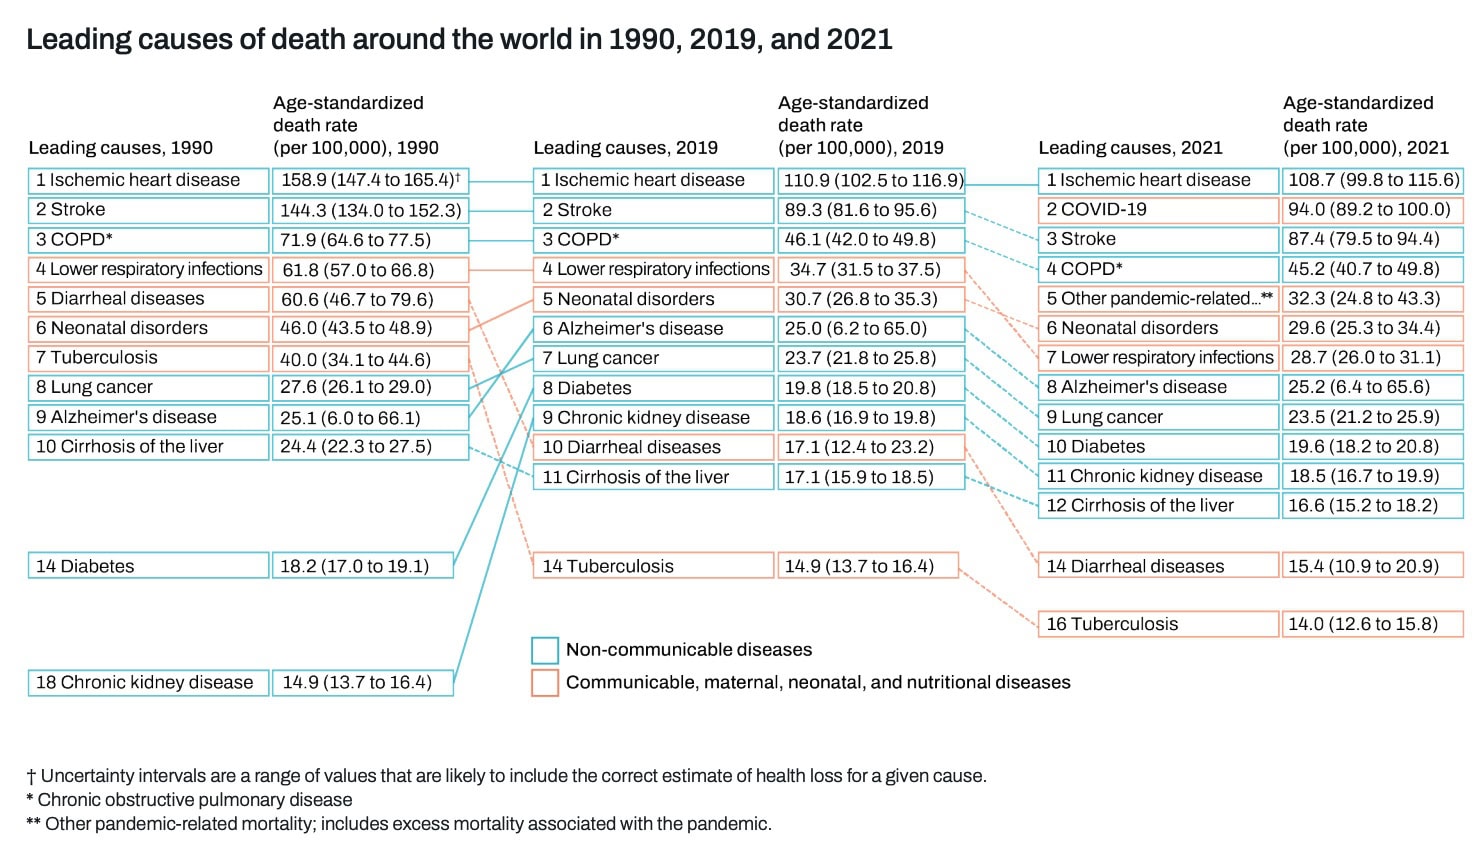

Epidemiologie

ACS ist weltweit die Hauptursache für Morbidität und Mortalität. Die Global Burden of Disease Study berichtet, dass ischämische Herzkrankheiten (einschließlich ACS) die führende Todesursache weltweit, die für fast 9 Millionen Todesfälle pro Jahr verantwortlich ist. Die Studie weist eine altersstandardisierte Todesrate von 108,7 pro 100.000 Personen aus. Leider war die ischämische Herzkrankheit 1990 weltweit die häufigste Todesursache, und daran hat sich im Laufe der Jahre nichts geändert.

Es scheint einige regionale Unterschiede zu geben. Die Prävalenz des akuten Koronarsyndroms ist in Ländern mit hohem Einkommen höher, aber der Zugang zu einer guten Gesundheitsversorgung einschließlich Prävention hat die Raten im Laufe der Jahre verbessert. Im Gegensatz dazu ist die Prävalenz von ACS in Ländern mit niedrigem und mittlerem Einkommen geringer, aber leider ist eine steigende Inzidenz zu beobachten, die auf eine Zunahme von Risikofaktoren wie Rauchen, Diabetes, Bluthochdruck,...